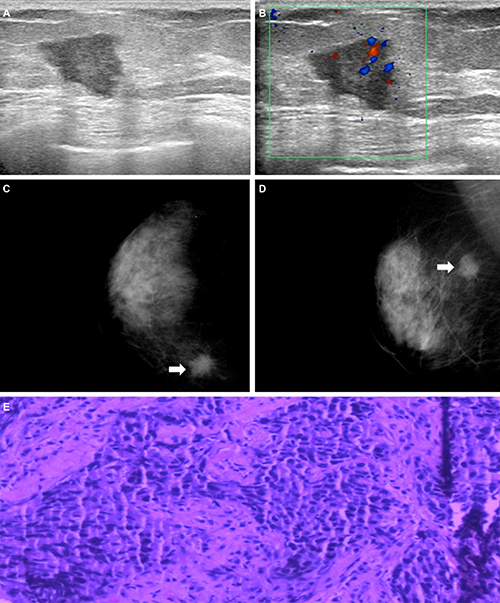

Representative cases are shown in Figure 1 and Figure 2. On the mammogram of the first case, there was a high density mass in the inner upper quadrant of the right breast and its border was spiculated. On ultrasound images we could find an irregular shape mass with circumscribed margin in a low echoic area. The mass size was 3.2 cm × 2.6 cm. The pathological findings confirmed it as invasive ductal carcinoma in nuclear grade 2 with lymphovascular invasion. Immunohistochemical findings were ER negative, PR negative, HER-2 (1+) negative. Because of its CK5/6 and EGFR were both negative, we defined it as NBC. Figure 2 showed an isodensity mass with circumscribed border in the inner upper quadrant of the left Breast. On the ultrasound, there was a mass with lobulated margin in hypoechoic. The mass size was 4.0 cm × 2.3 cm. Its posterior echo wasn’t attenuating and we couldn’t see any calcifications either. Spotty signals could be seen via Color Doppler. The pathological result confirmed invasive ductal carcinoma with a nuclear grade 3. Immunohistochemical findings were ER negative, PR negative, HER-2 (1+) negative. Because of CK5/6 positive, we considered it as BBC.

Figure 1: (A) and (B) Mammogram revealed a high density mass in the inner upper quadrant of the right breast (arrows) and its border was spiculated. (C) and (D) Ultrasound revealed an irregular shape mass with circumscribed margin in low echoic area. The mass size was 3.2 cm × 2.6 cm. Non-accentuating posterior echoes, non-calcification either. Spotty signals could be seen via Color Doppler. (E) Histopathological image showed it as invasive ductal carcinoma, original magnification, 200×; ER-, PR-, HER2 1+, CK5/6- and EGFR- showed it as NBC.